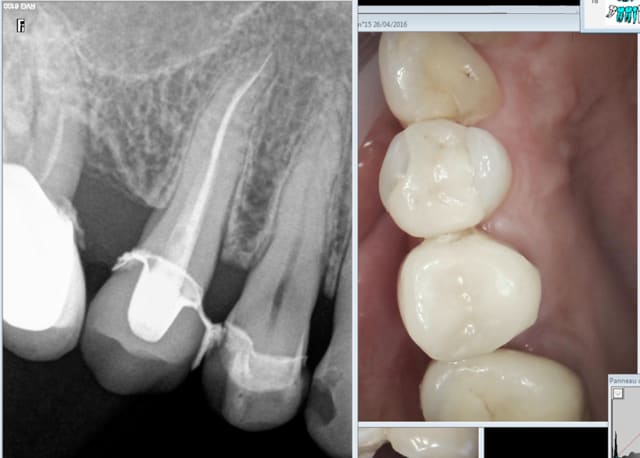

Remarque ca tient dans le temps à 9 ans ....

Tu me diras la ceram sur 25 du protho est bien pourrie aussi. -)

Aie 9 ans aussi. Ouh lalalala la cata. J'aurais du faire des radios après la pose il y a un binz en distal de la 36. -)))